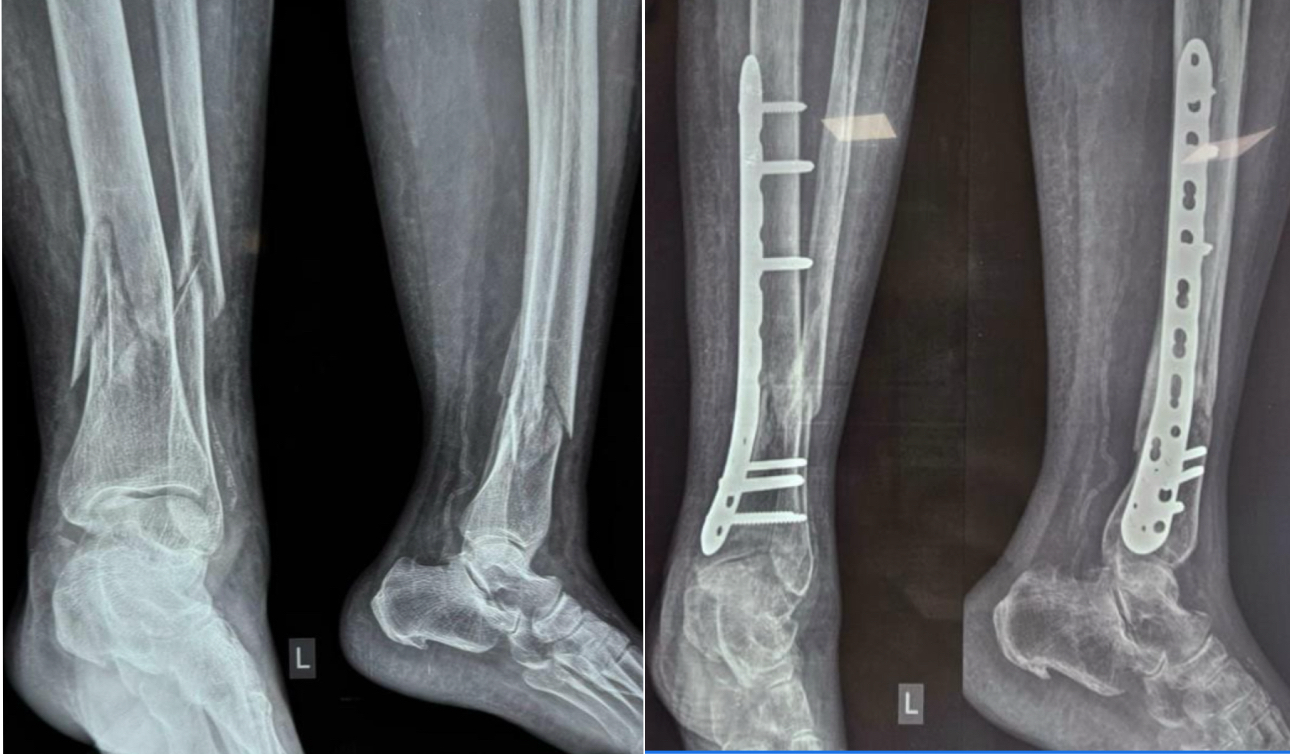

An anatomically pre-contoured distal tibial locking plate (3.5 mm system) was inserted through this tunnel and provisionally fixed with K-wires. The construct was then secured with a combination of locking and cortical screws under fluoroscopic guidance to ensure correct coronal and sagittal alignment without disturbing fracture biology. The wound was irrigated and closed in layers, with drains used selectively in cases of significant oozing. This technique follows AO foundation principles of biological fixation, emphasizing preservation of vascularity and minimization of soft tissue trauma [14]. Representative pre-operative and post-operative X-rays are shown in Fig. 3, while serial clinical follow-up images at immediate, 6 months, and 12 months are shown in Fig. 4. Functional recovery, including dorsiflexion and plantar flexion at 1-year follow-up, is illustrated in Fig. 5.

Figure 3: Pre-operative and post-operative X-rays (AO 43A3 fracture).